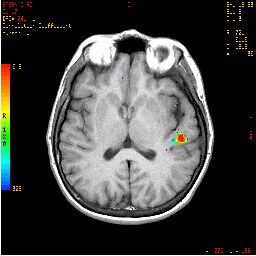

| Images | ![]() | ||||||

| Activation | Broca's area and left SMA are depicted. Some activation appears in the left hippocampal formation and visual areas. This last activation could be explained as the effect of picturing the objects given during the "ON" condition. There is also activation in the right cerebellum and left inferior temporal gyrus. |